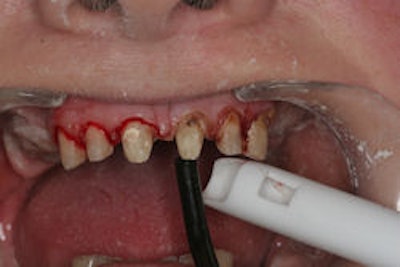

| Ozone advocates say the treatment can stop bleeding, as shown in this photograph of gingival plastic surgery done with an electrosurge, where the right side (from the viewer's perspective) was treated with ozone and the left side was not. Image courtesy of Jonathan Abenaim, D.M.D. |